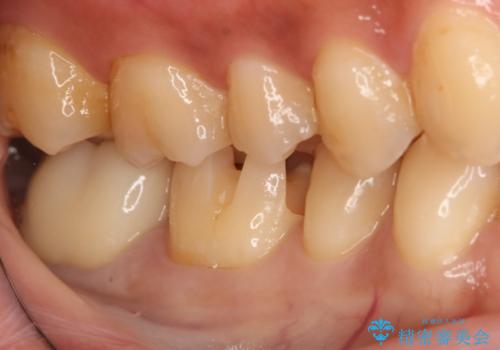

- 過去に他院で治療した部位が材料劣化を起こしていたため、セラミック治療を希望された患者様です。

切削量を考慮し、セラミックインレーを選択しました。

虫歯が深かったので、CRを詰めた上で形態を整えています。